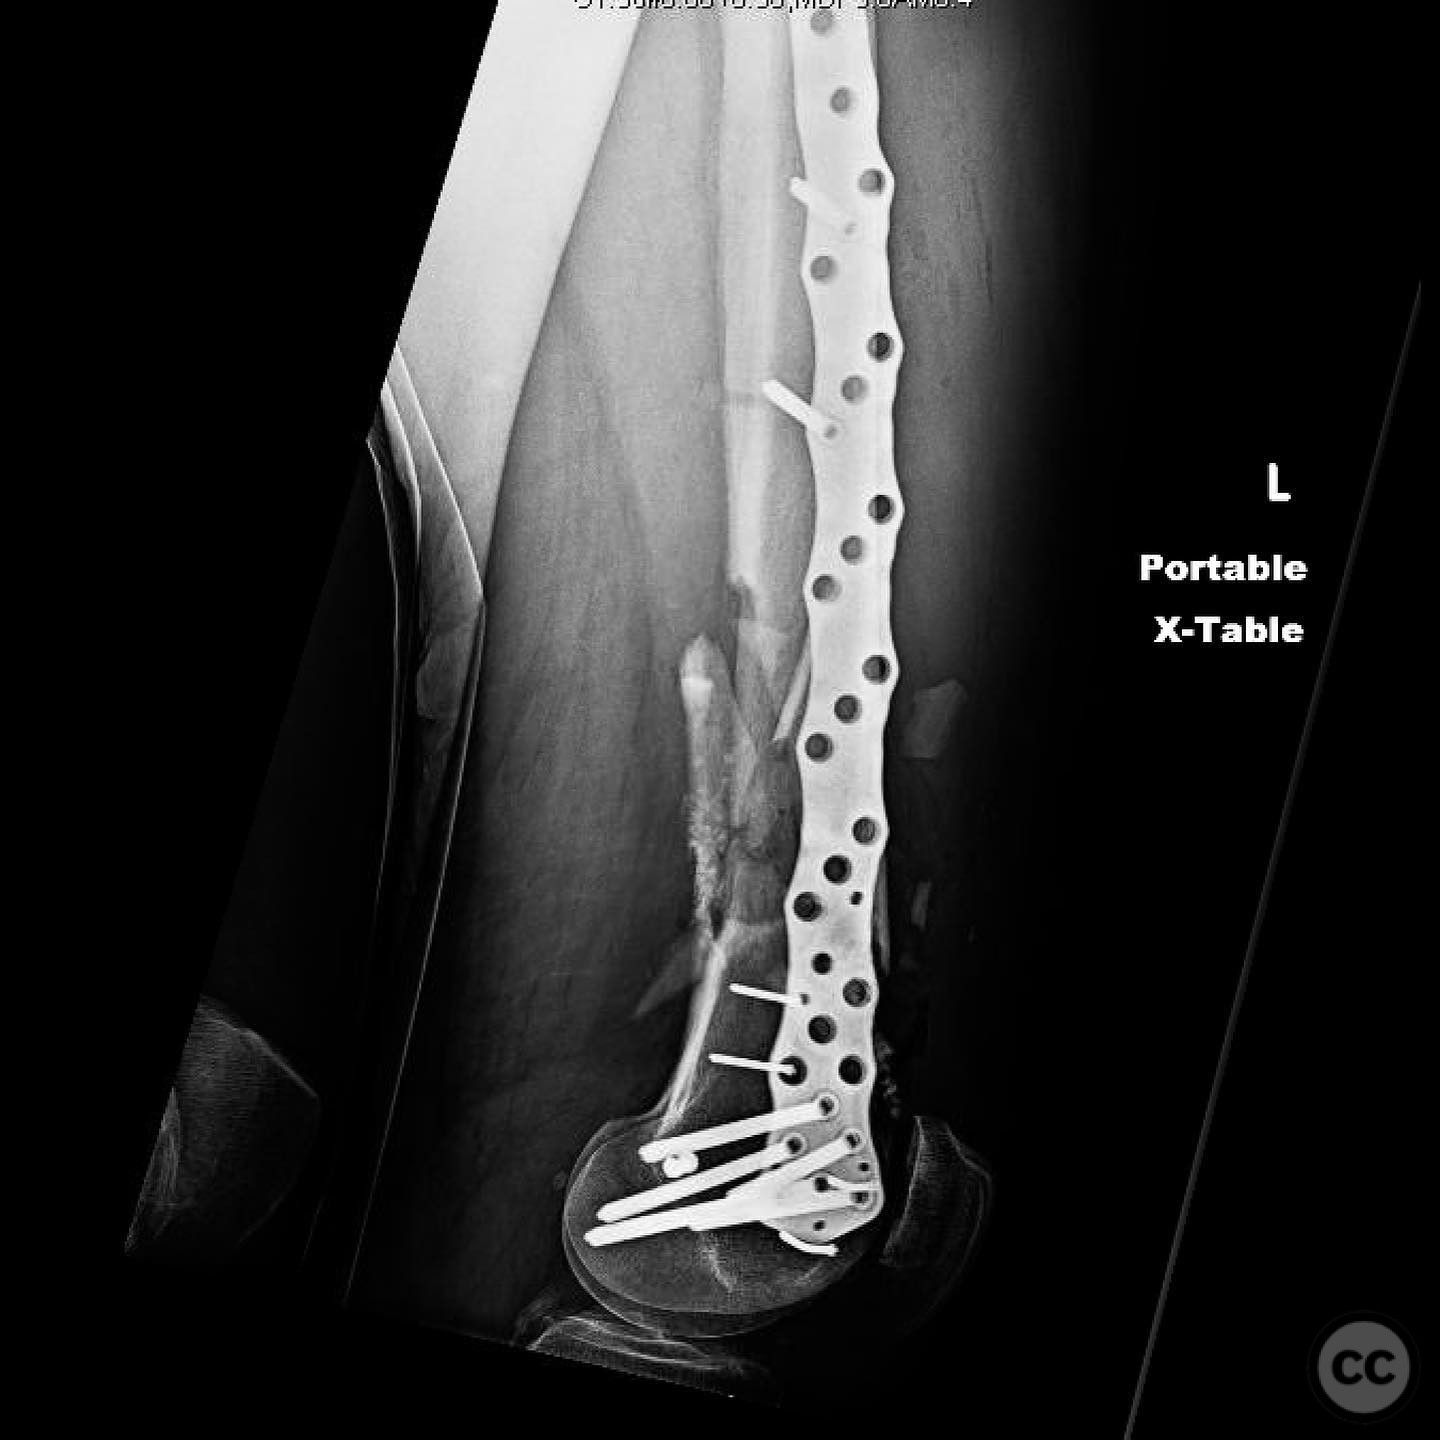

Anatomical surgical approach:  For the tibia, a longitudinal incision was made to access the proximal tibial start site for intramedullary nailing. Percutaneous clamps were utilized for reduction, supplemented by blocking screws as needed. For the distal femur, an external fixator was applied initially, followed by an in situ lateral approach for plating after reduction was achieved.

The tibial nailing required precise identification of the start site under fluoroscopic guidance, with percutaneous clamps aiding in reduction. Blocking screws were considered but not necessary due to successful reduction with clamps alone. The distal femur presented challenges in achieving coronal and sagittal alignment, necessitating reliance on the external fixator for reduction before proceeding with plating.

Orthopaedic implants used:   Intramedullary nail for tibia, external fixator for initial femoral stabilization, and locking plate for definitive femoral fixation.